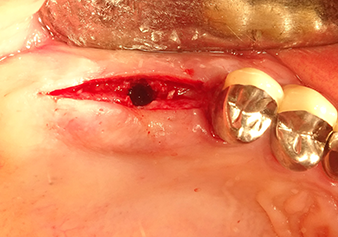

Following an intermediate check (Fig. 4) a further preparation step was performed (Fig. 5). Afterwards, the hydraulic Z35P instrument was used to lift the membrane to the desired position (Fig. 6 and 7). This was followed by further piezosurgical preparation of the implant bed, concluded with a rotary bur and shoulder milling cutter up to the implant diameter of 4.8 mm. Before the implant was inserted, the augmentation material (particle size approx. 0.8-1.6 mm) was introduced underneath the Schneiderian membrane (Fig. 8).

The implant bed is widened to 3.0 mm with the I3A instrument

Fig.5: In the next step, the implant bed is widened to 3.0 mm with the I3A instrument (power 100%, coolant 80%). The depth marks reliably prevent the preparation from going too deep.

The Schneiderian membrane is stretched 1.5-2 mm above the bony access

Fig.4: Intermediate check: The bone height above the maxillary sinus floor is approx. 4 mm palatal and buccal; the Schneiderian membrane is stretched 1.5-2 mm above the bony access.